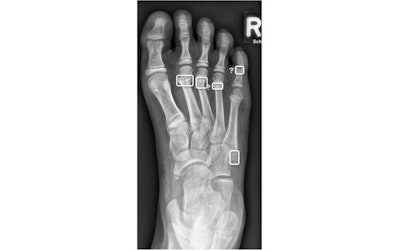

Radiograph of the right foot of an 8-year-old girl showing fractures of the distal second and third metatarsal bones. The AI incorrectly identified a false positive at the apophysis of the fifth metatarsal bone, as well as at the fourth metatarsal and proximal phalanx of the fifth toe. The latter two findings are marked with a question mark due to the AI’s low confidence level. Images available for republishing under Creative Commons license (CC BY 4.0 DEED, Attribution 4.0 International) and courtesy of the European Journal of Radiology.

The authors noted that more than half of the algorithm's false-positive findings for this cohort were attributable to the apophysis of the fifth metatarsal bone; they note that inexperienced readers often find distinguishing between fracture and apophysis in children is commonly challenging.